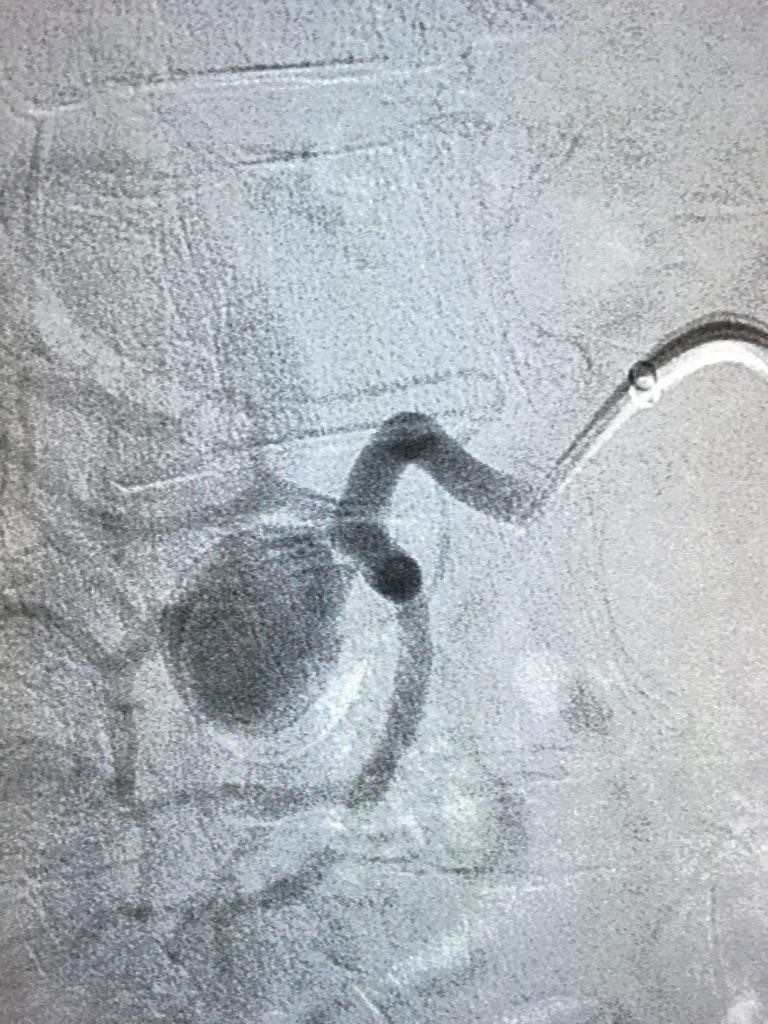

Tratamientos de varices:

- Cirugía clásica

- Métodos ablativos: Endoláser y Radiofrecuencia

- Métodos químicos: Microespuma, Pegamento (Venaseal)

- Tratamiento de arañas vasculares: Esclerosis microespuma, Crioesclerosis